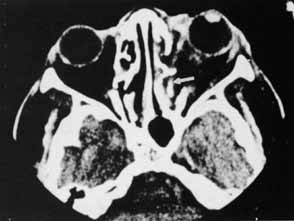

Of the adjunctive tests available, CT scan is the most useful in providing information about the presence and position of a foreign body relative to other structures in the orbit. Steel fragments 0.5 mm in diameter or larger74 and steel particles as small as 0.06 mm3 can be detected.75 Density measurements can be analyzed to distinguish metal, wood, glass, and air from surrounding tissue (Fig. 18). The appearance of wood may vary with the length of time in the orbit and the degree of hydration.76 In some cases, CT has not been able to detect wooden foreign bodies.77 Localization can best be achieved with the evaluation of axial and coronal views. Additional sagittal interpretations and three-dimensional reconstructions can be generated with available software.74 The diagnostic limitations of CT scans must be recognized; in some situations, accurate localization may be obscured by scatter artifact caused by metals or false-negative findings of radiolucent materials.

Fig. 18 A, Wood foreign body (arrow). B, Glass foreign body (arrow). C, Metal foreign body (arrow).